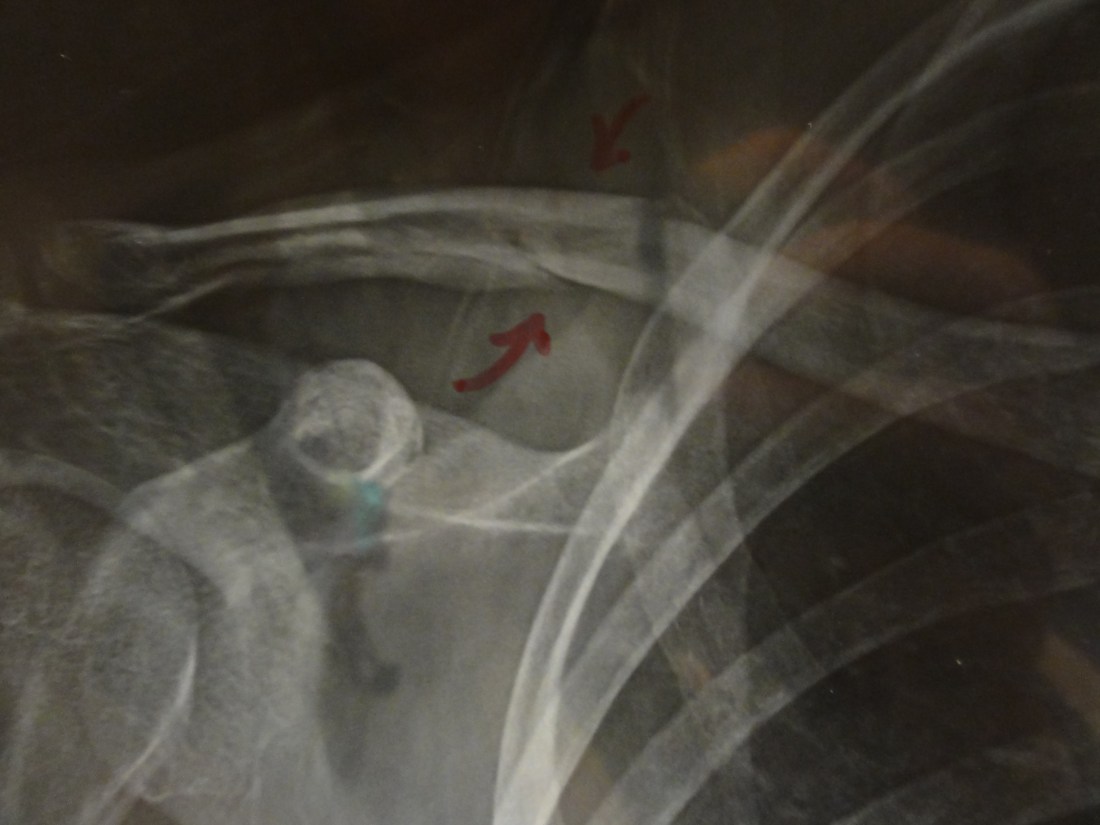

The orthopedist entered and showed me the x-ray, which now displayed two small, red arrows pointing at a fractured bone. Diagnosis? A fractured clavicle. Healing time? Six weeks. In a sling. On my dominant side. At this point, I was just grateful it wasn’t a break. And equally grateful for Lilia and Simon. My head was still not on straight, and Lilia knew all the questions to ask. Alternative options (an operation to insert a blade into the bone), length of time in the sling, follow-up appointments, etc.